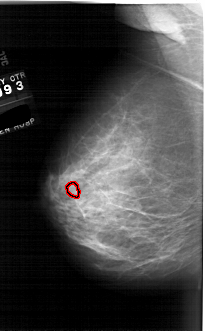

A_1761_1.LEFT_MLO

LEFT_MLO LINES 6271 PIXELS_PER_LINE 3886 BITS_PER_PIXEL 12 RESOLUTION 43.5 OVERLAY

FILE: A_1761_1.LEFT_MLO.OVERLAY

TOTAL_ABNORMALITIES 1

ABNORMALITY 1

LESION_TYPE MASS SHAPE OVAL MARGINS ILL_DEFINED

ASSESSMENT 4

SUBTLETY 3

PATHOLOGY BENIGN

TOTAL_OUTLINES 1

BOUNDARY